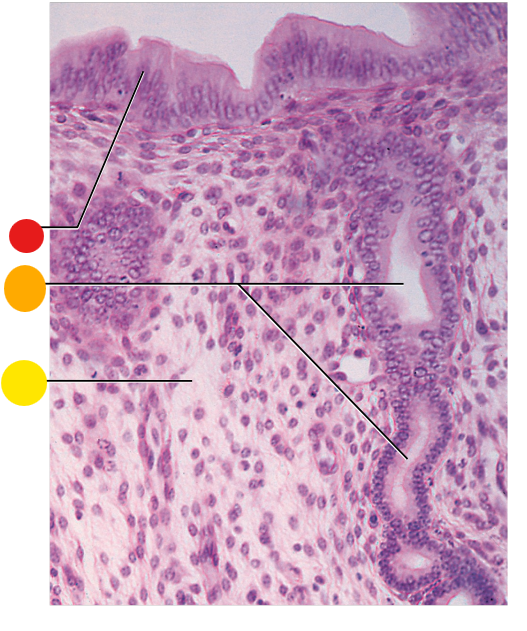

red

granulosa cells

orange

thecal cells

yellow

primary or secondary oocyte

light green

cumulus oophorus

dark green

antrum

what is this

tertiary follicle